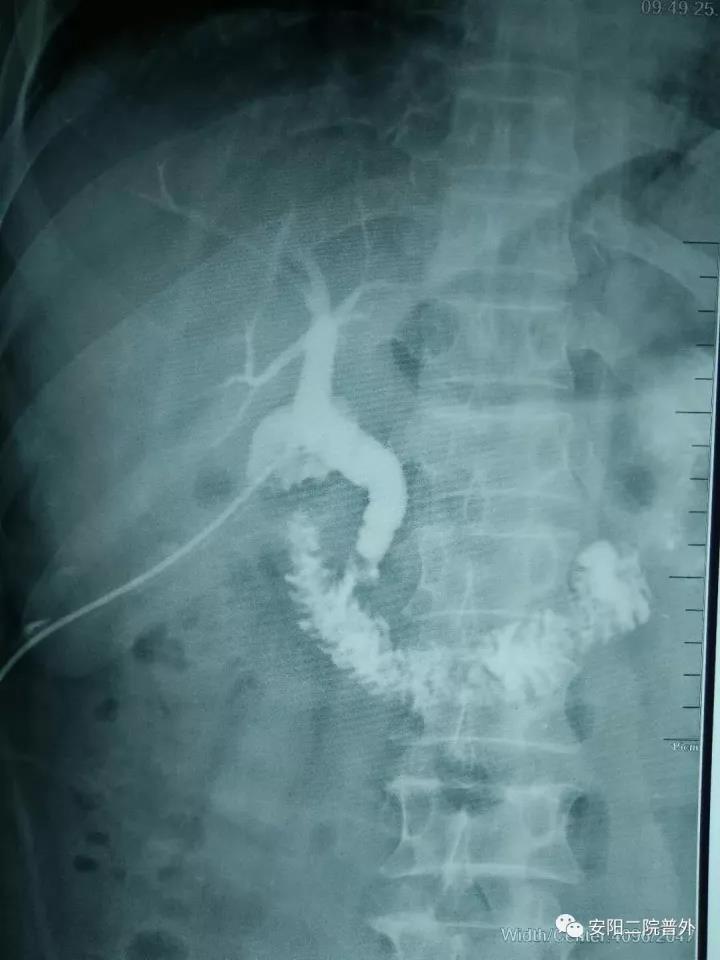

該例患者男性,52歲,外院行“膽囊切除+膽總管探查+T管引流術(shù)”,術(shù)后兩個(gè)月T管造影示:造影劑排入十二指腸受阻,膽總管擴張,膽總管下段見(jiàn)略低密度影,考慮膽總管下段結石?;颊哂诙嗉胰揍t院就診,因結石較大病情復雜未能入院治療。而后患者慕名找到普外科孟鈺主任,孟主任綜合評估后收住院,完善檢查后行膽道鏡檢查:術(shù)中見(jiàn)膽總管下段結石嵌頓,直徑約1.5cm,抓鉗及取石籃取石失敗,遂與泌尿外科張新軍主任聯(lián)合,行膽總管結石鈥激光碎石術(shù),將結石粉碎成小塊結石和粉末狀結石,取出小塊結石,將粉末狀結石沖洗入十二指腸,手術(shù)順利。目前患者康復出院。

內鏡下的膽總管結石

取石后